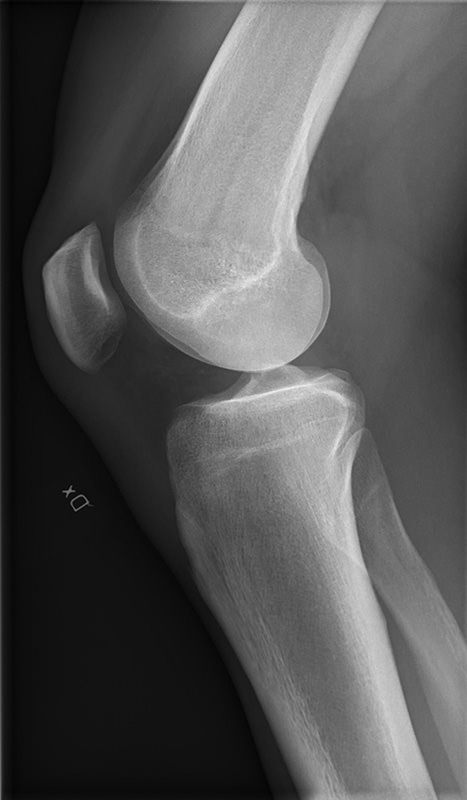

Il ginocchio è una articolazione che mette in rapporto il femore con la tibia ed il femore con la rotula. Queste superfici a contatto tra loro sono rivestite da uno strato di cartilagine più o meno spessa che favorisce lo scivolamento delle due superfici articolari.

L’articolazione femoro-tibiale è stabilizzata dai legamenti crociati (il Legamento Crociato Anteriore o LCA, ed il Legamento Crociato Posteriore o LCP) e dai legamenti collaterali (il Legamento Collaterale Mediale o LCM, ed il Legamento Collaterale Laterale o LCL). Nell’articolazione alloggiano i menischi mediale e laterale, strutture di fibrocartilagine che aumentano la stabilizzazione del Femore sulla Tibia, assorbendone parte delle sollecitazioni, come un ammortizzatore.

Le superfici di contatto sono contenute dalla capsula articolare, che è una struttura che possiamo immaginare quando vediamo un ginocchio gonfio: quell’espansione anomala intorno al ginocchio non è altro che la capsula che si è riempita di liquido sinoviale, che in condizioni fisiologiche viene prodotto in minime quantità per lubrificare e nutrire la cartilagine, mentre in condizioni patologiche, come per esempio una distorsione, va a riempire oltremodo l’articolazione.